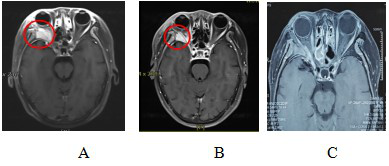

图9 眼眶ACC患者CIRT治疗前后MRI对比

Figure 9 Comparison of MRI before and after CIRT treatment for orbital ACC patients

Note: Figure 9A: MRI examination before CIRT treatment showed that: the right orbital space was occupied, and the boundary between the right orbital muscle and the external rectus muscle, lacrimal gland, and optic nerve was unclear, and the lateral wall of the orbit was invaded.

Figure 9B: MRI examination after CIRT treatment showed that: the right orbital space was occupied and abnormal enhancement, and the lateral orbital wall was invaded, which was smaller than that of the anterior lesion. The efficacy evaluation was PR.

Figure 9C: MRI examination 12 months after CIRT treatment showed that: the right orbital space was significantly reduced compared with the anterior lesion, and the efficacy evaluation was PR.